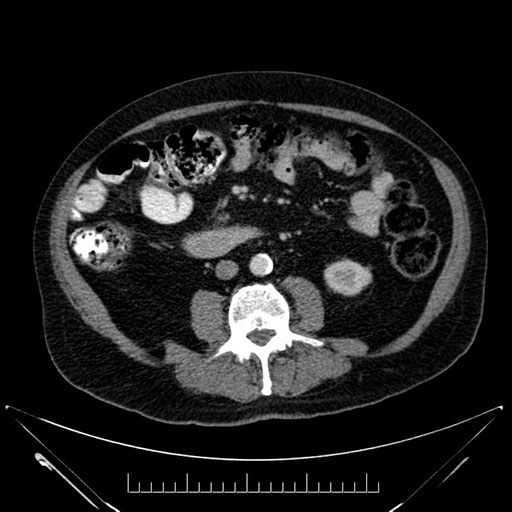

Axial - stented